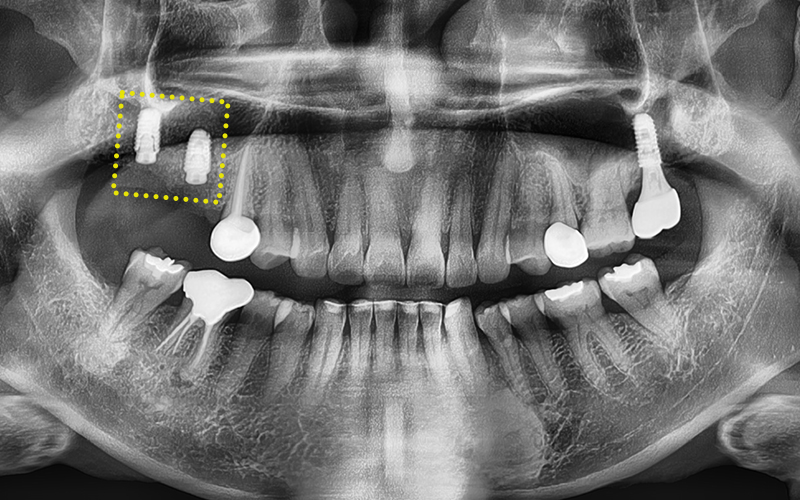

✅ Prosthetic restoration completed after treatment!

The prosthetic work has been completed precisely,

with careful consideration of the occlusion!

✅ Before > After

2024.11.22

▼ ▼ ▼

2025.04.15